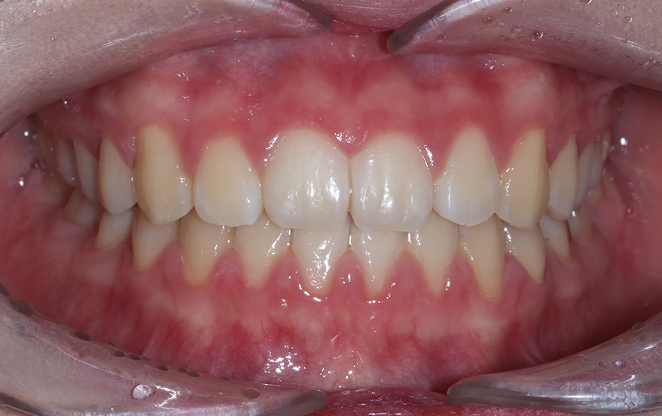

Before

After